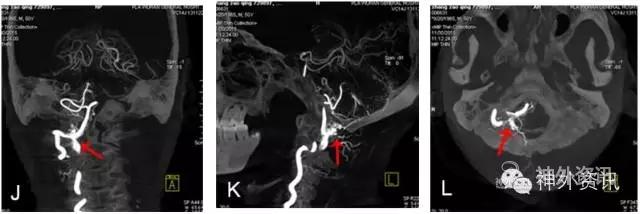

图4: J~L. 最大密度投影(MIP)冠状位、矢状位和轴位融合影像。

图4: M. 动态旋转MIP。

图4: N~P. MRI/3D-DSA 三维融合冠状位、矢状位和轴位融合影像。